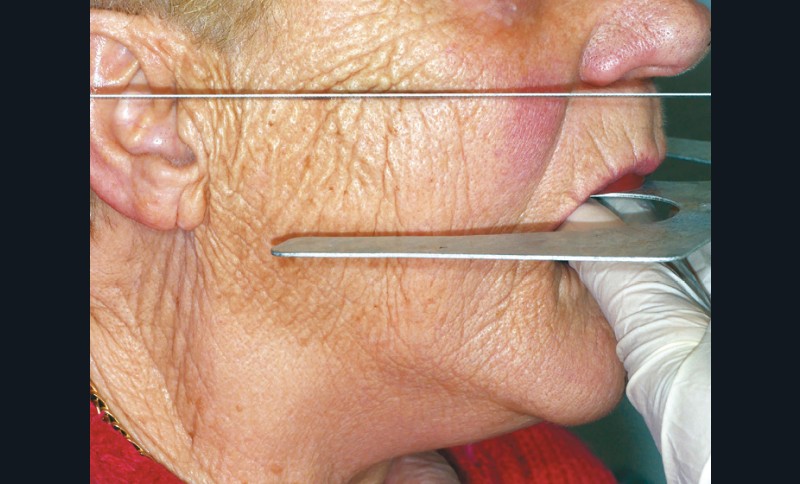

Le parallélisme entre la ligne bipupillaire et bourrelet est ensuite vérifié à l’aide du plan de Fox et d’une réglette métallique (fig. 9).